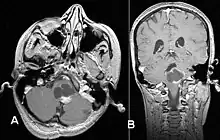

Pilocytic astrocytoma in the hypothalamic region

Axial non-contrast CT in a nine-year-old girl showing a slightly hypodense mass in the tectum of the brainstem, compressing the aqueduct of Sylvius and causing obstructive hydrocephalus

Sagittal T1-weighted MRI showing a well-circumscribed hypointense mass in the tectum (presumably a tectal plate glioma). These lesions are a distinct subset of pilocytic astrocytoma which present with hydrocephalus typically in 6 to 10 year-olds and are rarely progressive lesions. When imaging is characteristic, a biopsy is usually not performed because of the risks to adjacent structures, often shunting to relieve intracranial pressure is the only treatment required.

T1-weighted coronal MRI image postcontrast showing heterogeneous contrast enhancement within the presumed tectal plate glioma

Usually – depending on the interview of the patient and after a clinical exam which includes a neurological exam and an ophthalmological exam – a CT scan and/or an MRI scan will be performed to confirm the presence of a tumor. They are usually easily distinguishable from normal brain structures using these imaging techniques. A special dye may be injected into a vein before these scans to provide contrast and make tumors easier to identify. Pilocytic astrocytomas are typically clearly visible on such scans, but it is often difficult to say based on imaging alone what type of tumor is present.